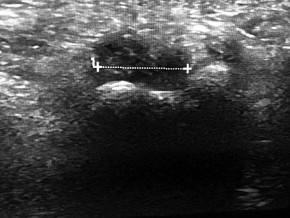

Question 19

A 28-year-old male sustains a closed comminuted tibial shaft fracture.

Two hours post-injury, he develops severe leg pain unyielding to narcotics. His blood pressure is 120/80 mmHg. Intracompartmental pressure monitoring is performed. Based on current guidelines, which measurement dictates an emergent 4-compartment fasciotomy?

Explanation

Acute compartment syndrome is classically defined by tissue hypoperfusion. The absolute compartment pressure is less reliable than the differential pressure (Delta P). A Delta P (Diastolic Blood Pressure minus Compartment Pressure) of less than 30 mmHg is an absolute indication for emergency fasciotomy, as capillary perfusion gradient is lost when tissue pressure approaches the diastolic pressure.